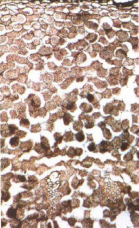

【标题】 两头尖 【拼音】 Liangtoujian 【英文】 RHIZOMA ANEMONES RADDEANAE 【概述】 本品为毛茛科植物多被银莲花Anemone raddeana Regel的干燥根茎。夏季采挖,除去须根,洗净,干燥。 【性味归经】 辛,热;有毒。归脾经。 【应用】 祛风湿,消痈肿。用于风寒湿痹,四肢拘挛,骨节疼痛,痈肿溃烂。 【贮藏】 置阴凉干燥处。 【用法用量】 1.5 ~3g。外用适量。 【理化鉴别】 (1) 本品横切面:表皮细胞 1列,切向延长,外壁增厚。皮层由10余列类圆形薄壁细胞构成。维管束外韧型,10余个排成环状,韧皮部细胞皱缩,木质部导管 6 ~24个,形成层不明显。射线宽阔,髓部较大,为类圆形薄壁细胞构成。薄壁细胞充 满淀粉粒。 粉末灰褐色。淀粉粒众多,单粒类圆形或椭圆形,直径2~11μm,脐点点状或短缝状,层纹不明显;复粒由2~4分粒组成。表皮细胞红棕色、黄色或亮黄色,外壁木栓化 增厚,常呈脊状或瘤状突入细胞内。网纹、螺纹或梯纹导管多见,直径10~33μm,少有 具缘纹孔导管。 (2) 取本品粗粉2g,加甲醇10ml,置水浴上微温,振摇10分钟,滤过,取滤液2ml,加 1%氢氧化钠溶液2ml,置水浴上加热3 分钟,溶液呈澄明的鲜黄色,再加 1%盐酸溶 液使成酸性,溶液鲜黄色消褪,生成乳白色混浊。 (3) 取本品粗粉1g,加70%乙醇10ml,置水浴上微沸10分钟,滤过,取滤液2ml,蒸干,加醋酐1ml 使溶解,沿壁缓缓加入硫酸,界面即显紫红色,放置,上层显污绿色。 【性状】 本品呈类长纺锤形,两端尖细,微弯曲。其中近一端处较膨大。长 1~3cm,直径2~7mm。表面棕褐色至棕黑色,具微细纵皱纹,膨大部位常有1~3个支根痕呈 鱼鳍状突起,偶见不明显的3~5环节。质硬而脆,易折断,断面略平坦,类白色或灰褐 色,略角质样。无臭,味先淡后微苦而麻辣。 【图片】 两头尖 ![]() 多被银莲花 ![]() 药材两头尖 ![]() 药材两头尖横切面 ![]() (责任编辑:Doctor001) |